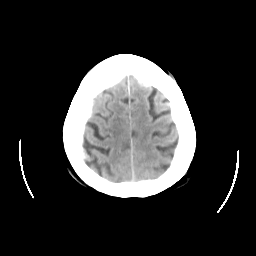

CT Study #2 -- Slice #24